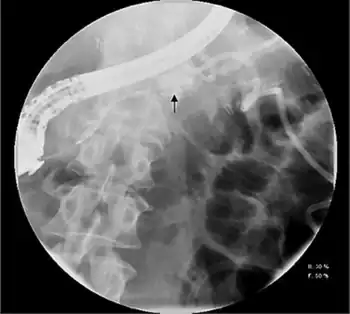

.png)

Pleural or ascitic fluid should be sent for analysis. An elevated amylase level, usually > 1,000 IU/L, with protein levels over 3.0 g/dL is diagnostic. Serum amylase is often elevated as well, due to enzyme diffusion across the peritoneal or pleural surface.[1][2] Contrast-enhanced computed tomography and endoscopic retrograde cholangiopancreatography (ERCP) may also assist in diagnosis, with the latter an essential component of treatment.